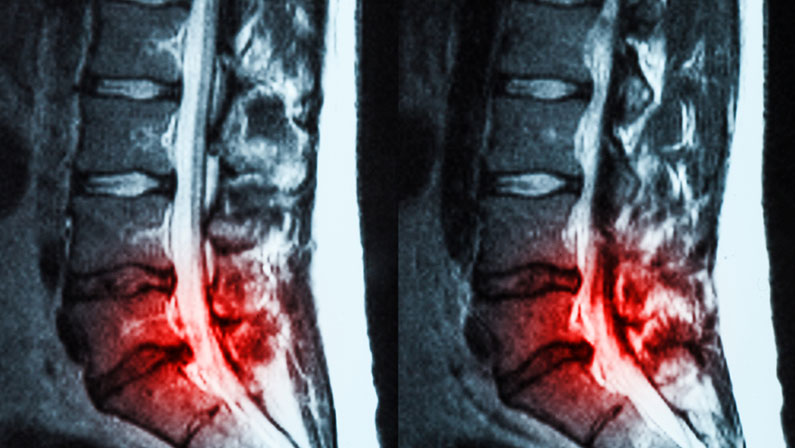

A CT (Computed Tomography) scan is a medical imaging procedure that combines X-ray measurements taken from different angles around the body and uses computer processing to create cross-sectional images (slices) of bones, blood vessels, and soft tissues. These detailed images help doctors see the inside of the body with greater clarity than traditional X-rays.

CT scans are particularly useful for detecting bone abnormalities, soft tissue injuries, and detailed internal structures. They are often used when other imaging techniques, like X-rays or MRIs, are inconclusive.

CT scans offer unique advantages over other imaging techniques. While MRIs are excellent for visualizing soft tissues and identifying conditions like herniated discs or spinal cord issues, CT scans excel in showing bone structures and detecting fractures. For patients with lower back pain, a CT scan can quickly and accurately identify issues related to the vertebrae or surrounding structures.